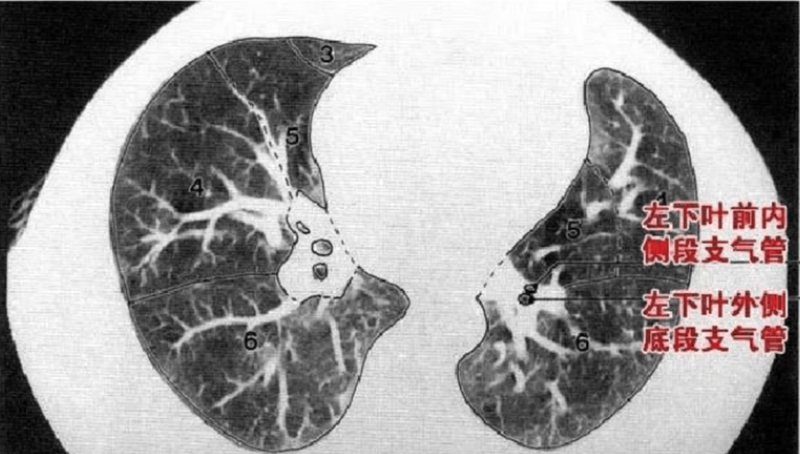

下叶: S6:背段;S7∶内基底段;S8:前基底段;S9:外基底段;S10:后基底段。

下叶:S6:背段;S7+8:前内基底段;S9:外基底段;S10:后基底段